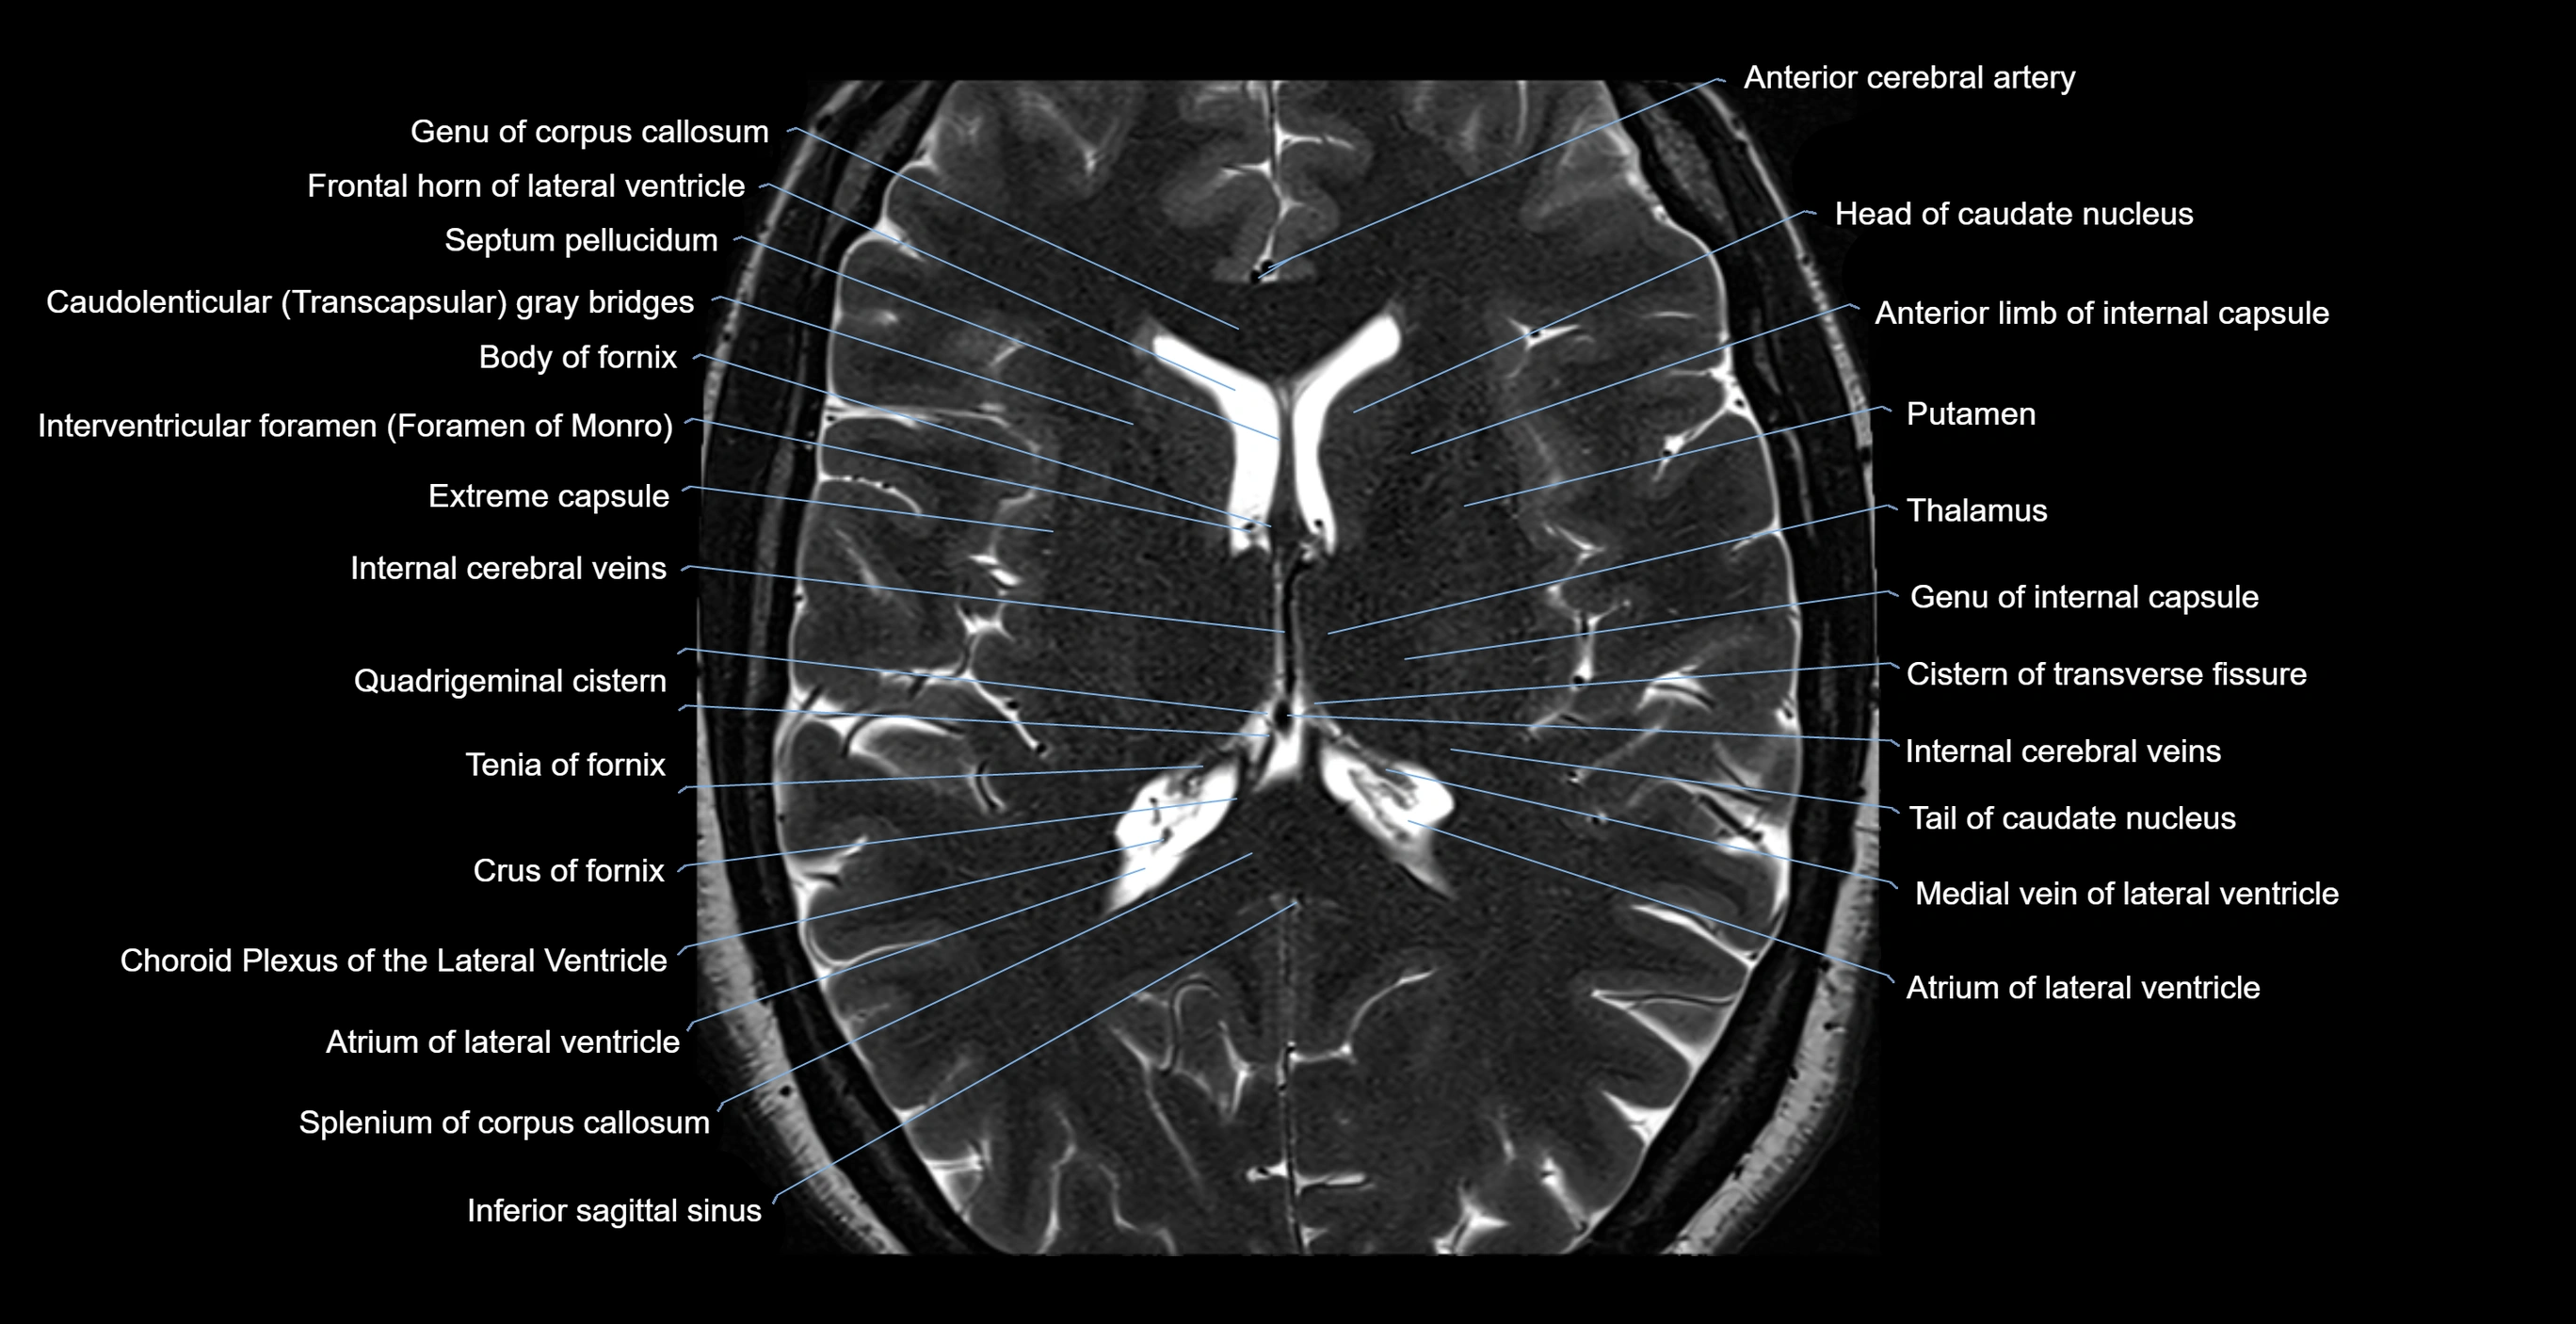

- Atrium of lateral ventricle

- Body of fornix

- Body of lateral ventricle

- Caudatolenticular gray bridges

- Choroid plexus of the lateral ventricle

- Cistern of transverse fissure

- Column of fornix

- Crus of fornix

- Culmen

- Extreme capsule

- Frontal horn of lateral ventricle

- Genu of corpus callosum

- Head of caudate nucleus

- Inferior sagittal sinus

- Internal cerebral vein

- Interthalamic adhesion

- Interventricular foramen

- Medial vein of lateral ventricle

- Occipital horn of lateral ventricle

- Pulvinar

- Putamen

- Septum pellucidum

- Splenium of corpus callosum

- Straight sinus

- Tail of caudate nucleus

- Tenia of fornix

- Thalamus

- Third ventricle